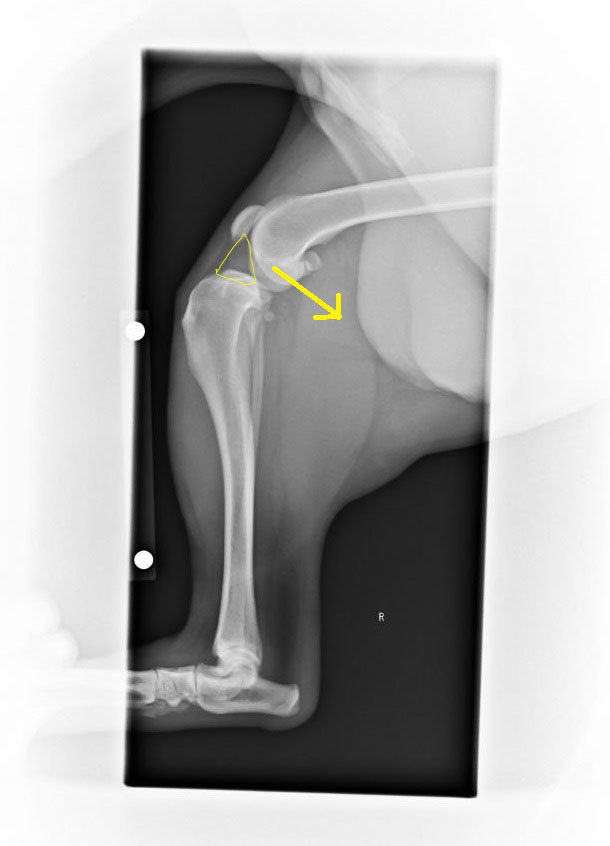

※↓ 実際の いちくんの膝関節レントゲン。

△部分、関節を潤滑する役目の関節液の増量所見があり、

大腿骨が脛骨の丸い先端を滑り落ちて内側にあるのが分かりますね。